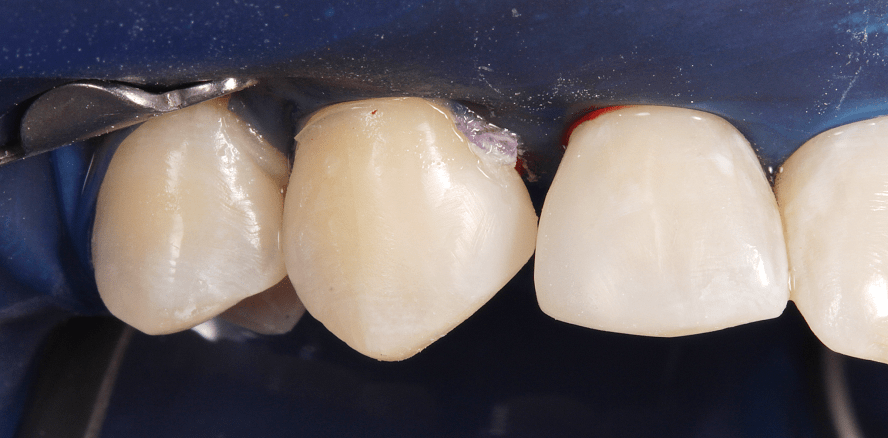

Adhäsivrestaurationen mit Komposit an 12/13 und 22/23 zum Schluss des Diastema laterale (Abb. 6–8).

Grundsätzlich stand die Frage einer Gesamtsanierung (Austausch der insuffizienten Füllungen, Kariesentfernung 15, 14) zur Diskussion. Die Patientin wünschte sich jedoch lediglich den Diastemaschluss im seitlichen Frontzahnbereich und möchte die weitere Versorgung beim Hauszahnarzt in Brasilien fortführen lassen. Nach Abwägung sowohl ethischer als auch finanzieller Aspekte entschied sich die Patientin vorerst nur für die Korrektur/Verbesserung der Smile-Line im Oberkiefer mit direkten freihändig geschichteten Kompositaufbauten an 13, 12 sowie 22, 23. Konservierende (Füllungstherapie, In-Office-Bleaching), kieferorthopädische (Aligner-Therapie) und prothetische (Additional Veneers an 2ern und 3ern) Maßnahmen möchte sie aus finanziellen Überlegungen vorerst zurückstellen.4,5

Die Zahnproportionen sind insbesondere im 2er-Bereich „ausgeprägt“ dreieckig und sollten als Kompromiss betrachtet werden. Durch den Lückenschluss mit Komposit dürften die Interdentalpapillen noch weiter ausreifen und damit das dreieckig imponierende Erscheinungsbild der seitlichen Schneidezähne deutlich abschwächen. Bei den Eckzähnen hat sich durch die „Verbreiterung“ nach mesial eine Verlängerung der Schneidekante (Schenkel) und somit eine „umgekehrt imponierende Anatomie“ des 3ers ergeben. Dies hätte durch eine zusätzliche Formanpassung in Komposit mit einem zusätzlichen Aufwand korrigiert werden können, wurde jedoch von der Patientin abgelehnt.6 Für sie ist das Ergebnis sehr zufriedenstellend. Für den Behandler, als Kompromiss, stellt sich die Behandlung ebenso als Erfolg dar.